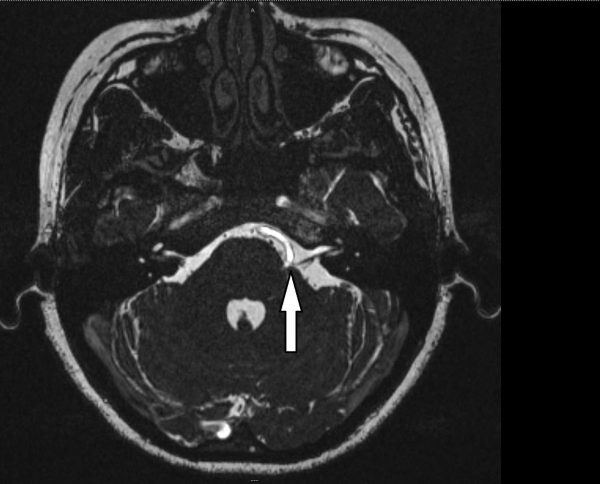

我先给琦琦做了磁力共振扫描,报告正常,大脑内没有肿瘤,但却看到脑干血管膨胀弯曲,压迫左边颜面神经线的出口处,造成神经线受压,引起左侧面肌痉挛。

要解决琦琦的问题,我建议以微血管和神经线减压术(Microvascular decompression, MVD),从根本上进行治疗。

这是一项微创手术,从耳朵后面的头颅上钻开小孔,经过小脑和大脑,找到膨胀弯曲的血管,将之挪开,然后在颜面神经线的出口处放一小块医疗用特氟龙(Teflon),避免神经线受挤压。